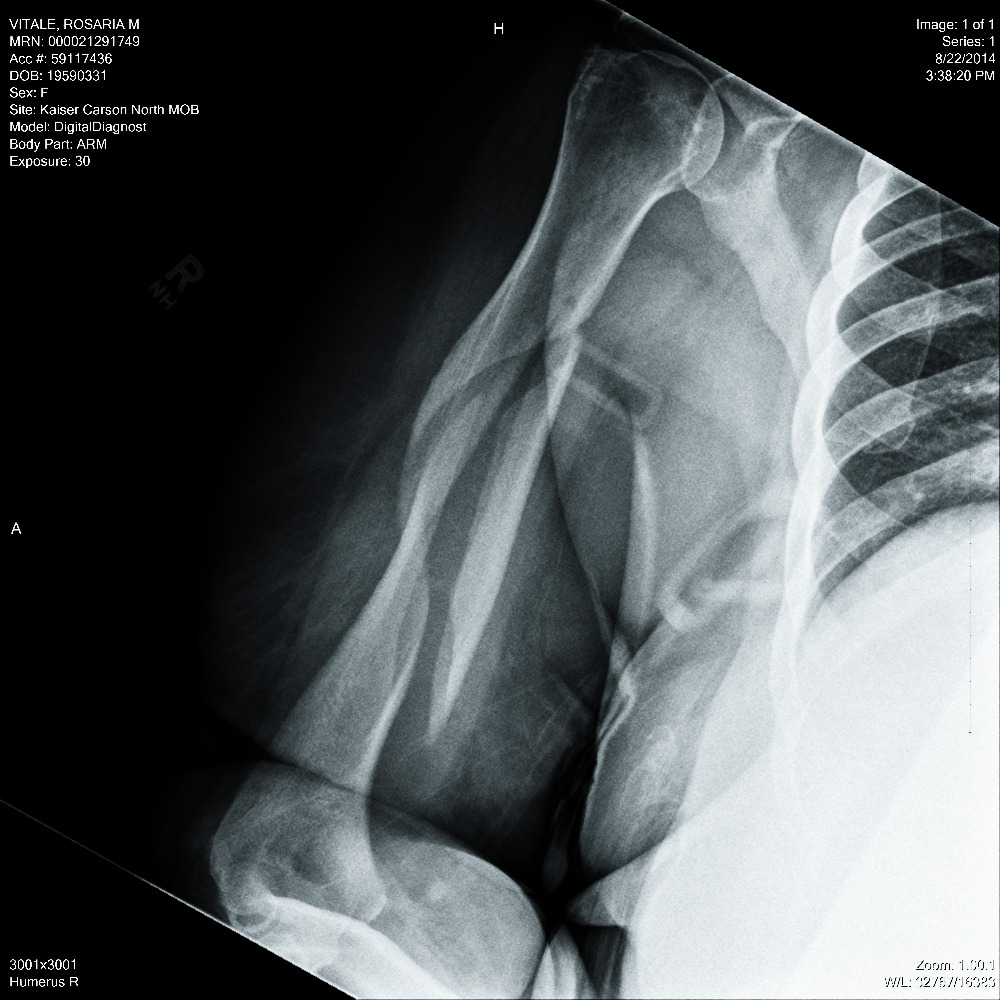

I was taken away in an ambulance to the ER . After many hours of waiting, tests, scans and an Xray, I got the bad news. My right humerous was broken in THREE places. Oh my lord! You can see the break in the X-ray photo. What do I do? Where do I go? I had no insurance. They couldn't put a cast on because of the location and nature of the break. I left the hospital with cut up clothes, stitches above my left eye, a sling and 3 pain pills!